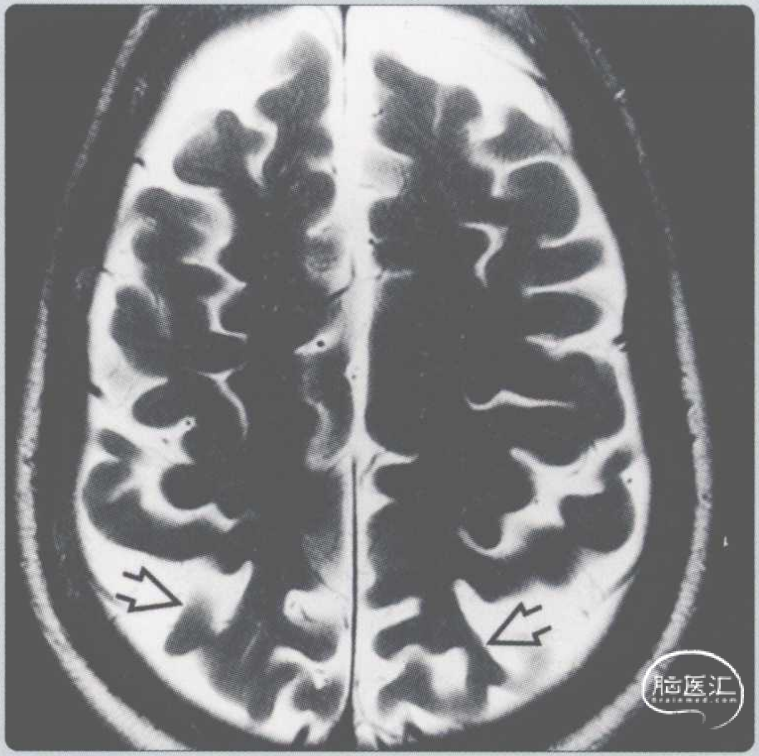

【影像时间·253】一位患有痴呆和视觉忽视的62岁女性患者